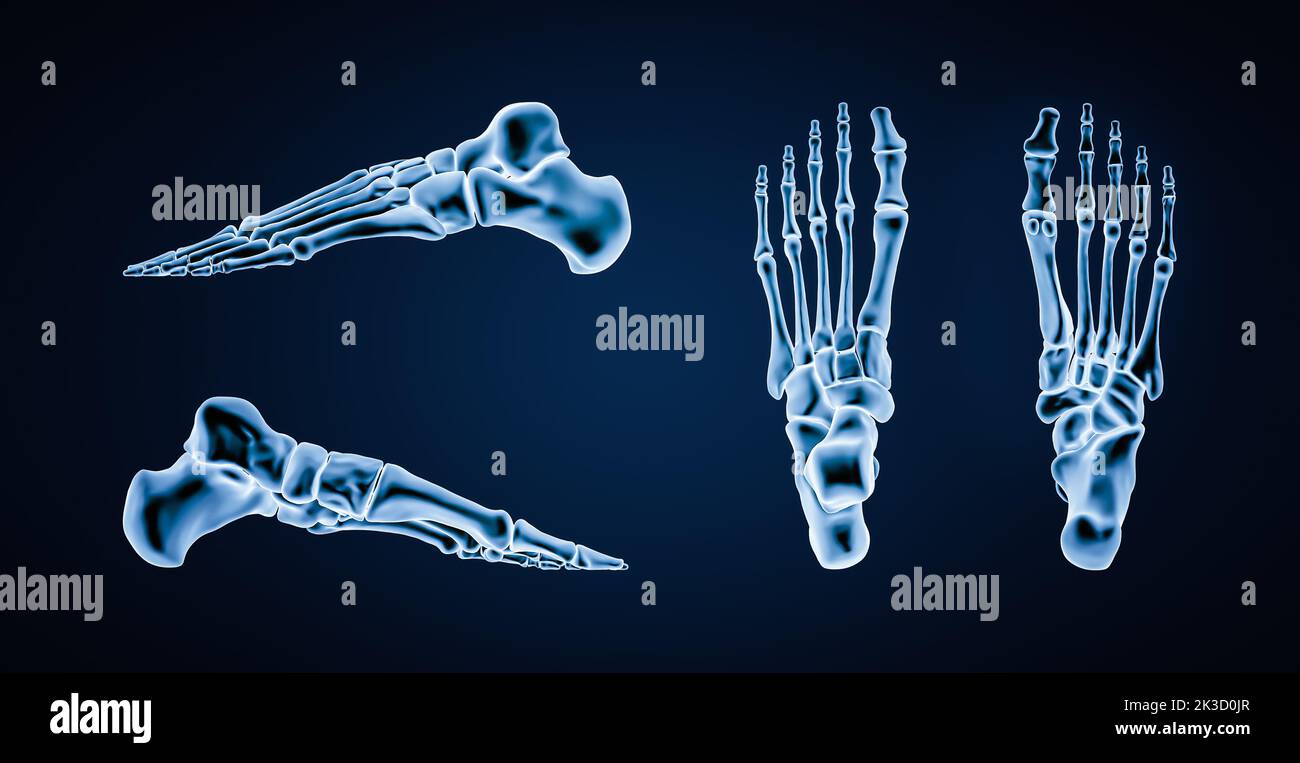

RF2K3D0JR–OS précis des os du pied gauche humain ou squelette 3D illustration du rendu. Vues latérales, médiales, dorsales et plantaires. Anatomie, ostéologie, squelette

RF2K1RE44–Vue latérale ou en profil d'os précis du pied gauche humain avec contours du corps sur fond bleu 3D illustration de rendu. Anatomie, ostéologie, ortho

RF2K1RE43–Vue inférieure ou inférieure d'os précis du pied gauche humain avec contours du corps sur fond bleu 3D illustration de rendu. Anatomie, ostéologie, ortho

RF2K1RE45–Vue supérieure ou supérieure d'os du pied gauche humains précis avec contours du corps sur fond bleu 3D illustration de rendu. Anatomie, ostéologie, orthopédie

RF2K3D0JD–Vue intérieure médiane ou profil des os du pied gauche humains précis isolés sur fond bleu 3D illustration de rendu. Anatomie, ostéologie, orthopédiste